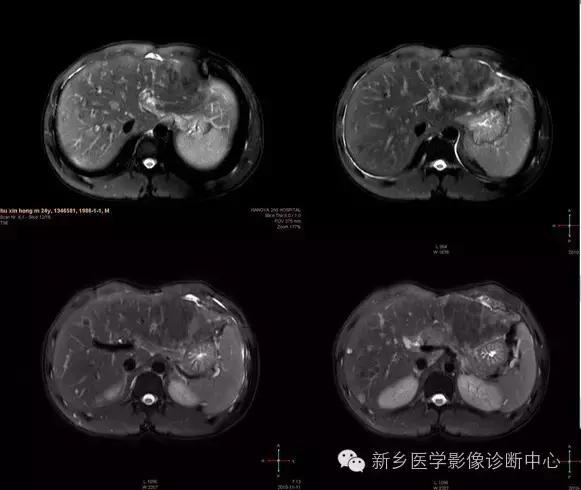

肝脏黑色素瘤

原发于肝脏的恶性黑色素瘤极其罕见。肝脏原发恶性黑色素瘤临床表现及体征均无特征性,与其他肝脏占位性、 肿瘤性病变无法区分,此为该病的临床特征。

肝脏恶性黑色素瘤的超声和 CT多表现为肝脏增大,肝内单发、 多发占位病变或弥漫性、 结节性改变, 占位性病变可为实性、 囊性、 囊实性改变,但上述改变无明显特异性, 与其他肝脏恶性肿瘤无法区分。MR T1 加权呈高信号、 T2 加权呈低信号